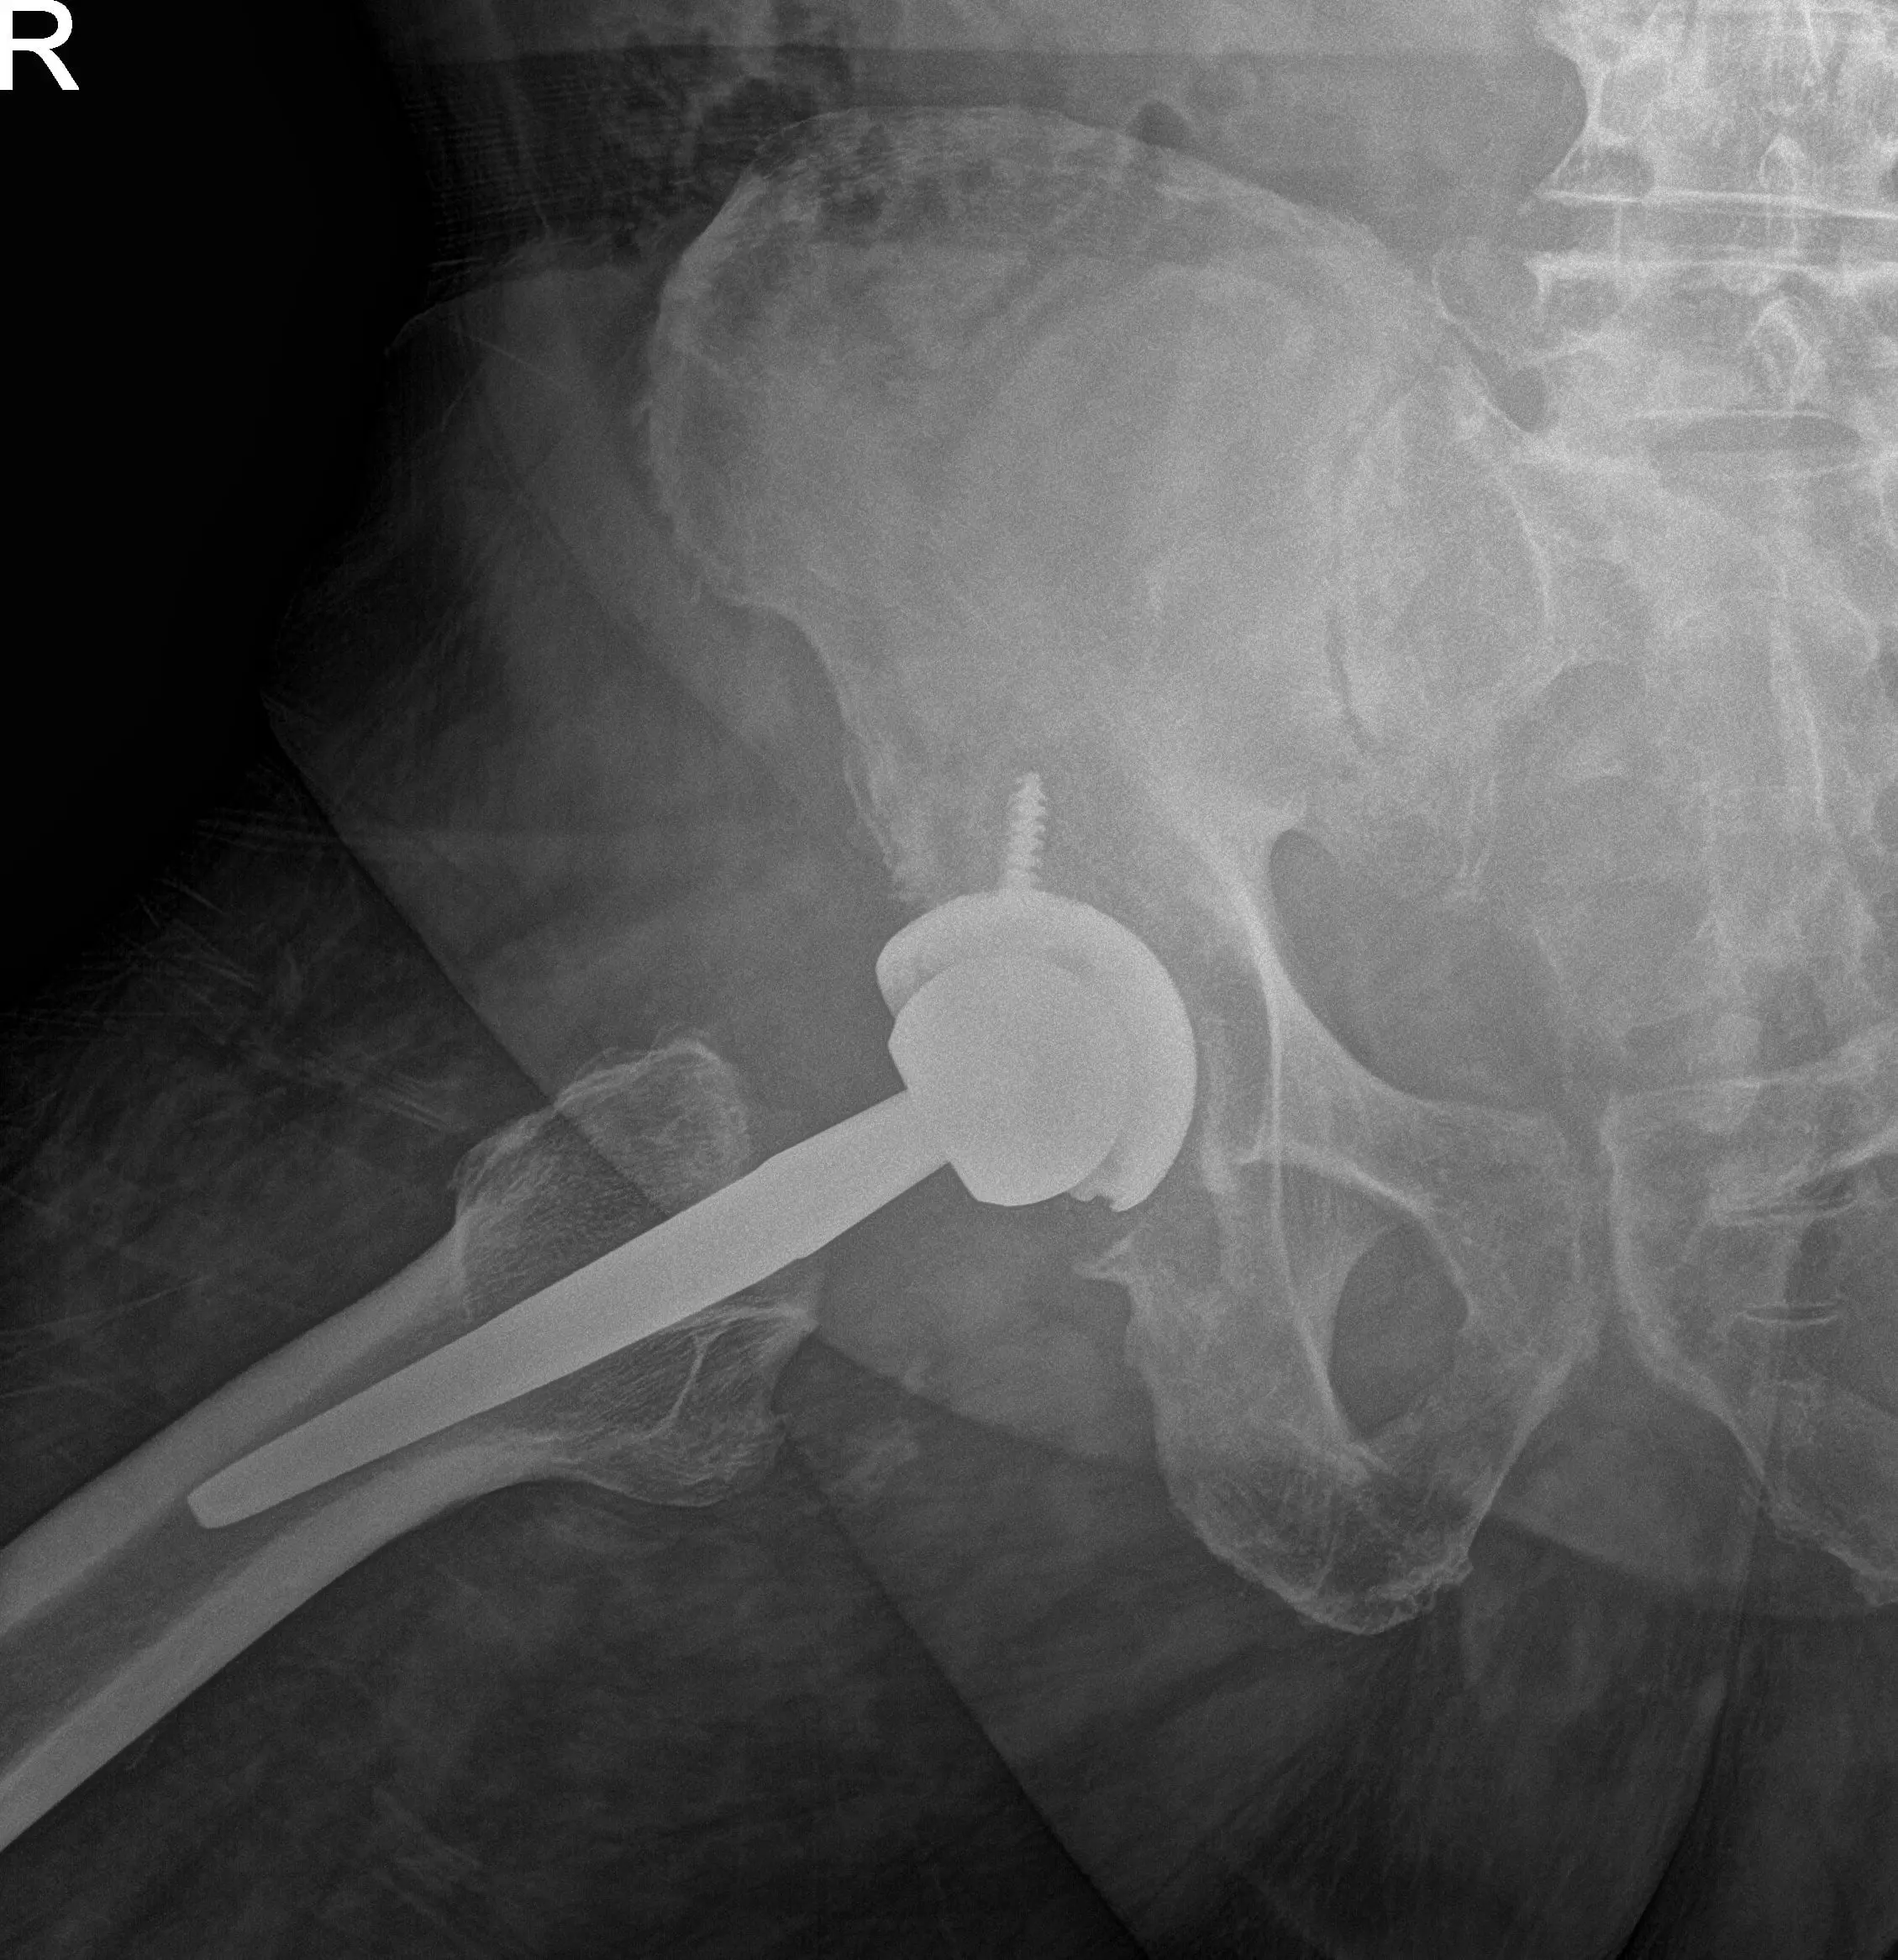

Preoperative X-ray images showing AP and frog-leg lateral view of the right hip